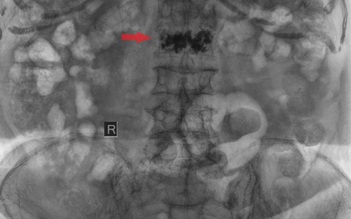

Cần lưu ý gì khi bơm xi măng sinh học trong điều trị xẹp đốt sống?

Kỹ thuật bơm xi măng sinh học đang mở ra bước tiến mới trong điều trị xẹp đốt sống do loãng xương, không chỉ giúp người bệnh thoát khỏi những cơn đau dữ dội mà còn nhanh chóng lấy lại khả năng vận động, giảm thiểu rủi ro so với phẫu thuật truyền thống.

Bơm xi măng sinh học cứu cụ bà 100 tuổi bị té ngã, chấn thương cột sống